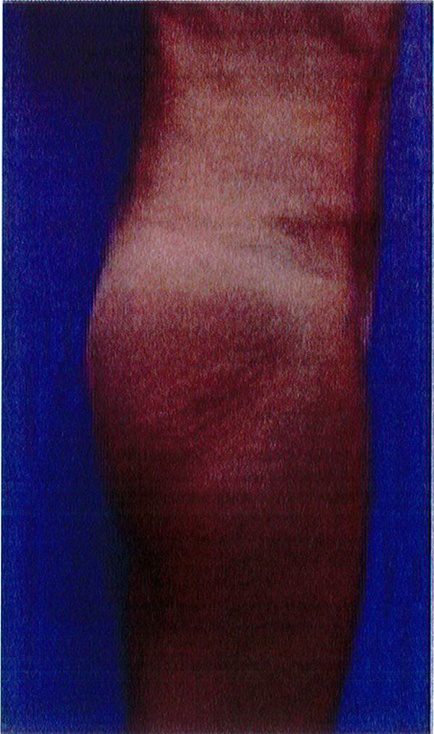

Hình. 18.. (A) Hình anh trước và (B) và sau phẫu thuật làm đầy mông của bệnh nhân được đặt khối implant dưới cân thể tích 225 mL, hai bên.

Bệnh nhân 31 tuổi tiền sử khỏe mạnh, có chỉ định nâng mông bằng implant do thiếu hụt thể tích. Hai khối anatomic implant 225 mL polyurethane dạng gel được đặt ở vị trí dưới cân. Sau phẫu thuật không ghi nhận biến chứng trong suốt quá trình hồi phục, vết mổ liền tốt (Hình 18).